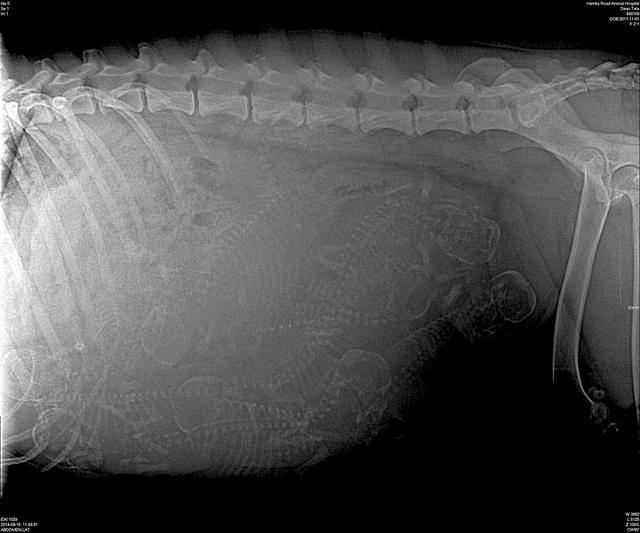

Tela preg xray day 58 preg 1

How many puppies can you count ( Hint count skulls if you can see them!)